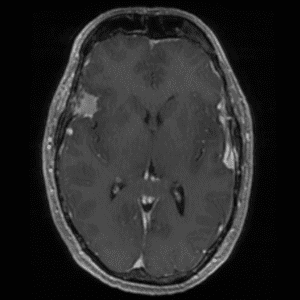

Case #14

CNS toxoplasmosis